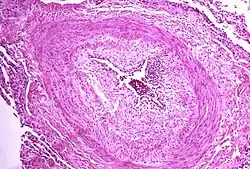

The pathogenesis of pulmonary arterial hypertension (WHO Group I) involves the narrowing of blood vessels connected to and within the lungs. This makes it harder for the heart to pump blood through the lungs, as it is much harder to make water flow through a narrow pipe as opposed to a wide one. Over time, the affected blood vessels become stiffer and thicker, in a process known as fibrosis. The mechanisms involved in this narrowing process include vasoconstriction, thrombosis, and vascular remodeling (excessive cellular proliferation, fibrosis, and reduced apoptosis/programmed cell death in the vessel walls, caused by inflammation, disordered metabolism and dysregulation of certain growth factors).[27][28] This further increases the blood pressure within the lungs and impairs their blood flow. In common with other types of pulmonary hypertension, these changes result in an increased workload for the right side of the heart.[16][29] The right ventricle is normally part of a low pressure system, with systolic ventricular pressures that are lower than those that the left ventricle normally encounters. As such, the right ventricle cannot cope as well with higher pressures, and although right ventricular adaptations (hypertrophy and increased contractility of the heart muscle) initially help to preserve stroke volume, ultimately these compensatory mechanisms are insufficient; the right ventricular muscle cannot get enough oxygen to meet its needs and right heart failure follows.[16][28][29] As the blood flowing through the lungs decreases, the left side of the heart receives less blood. This blood may also carry less oxygen than normal. Therefore, it becomes harder and harder for the left side of the heart to supply sufficient oxygen to the rest of the body, especially during physical activity.[30][31][11] During the end-systolic volume phase of the cardiac cycle, the Gaussian curvature and the mean curvature of the right ventricular endocardial wall of PH patients were found to be significantly different as compared to controls.[32]

In PVOD (WHO Group I), pulmonary blood vessel narrowing occurs preferentially (though not exclusively) in post-capillary venous blood vessels.[33] PVOD shares several characteristics with PAH, but there are also some important differences, for example differences in prognosis and response to medical therapy.[34]